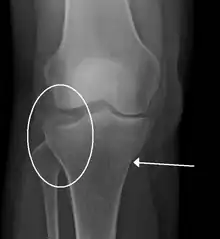

![]() | |

| A severe tibial plateau fracture with an associated fibular head fracture | |